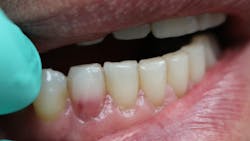

ECR can be differentiated from root caries due to its pink hue and tactile sensation. During the examination, you will find that the dentin surrounding an ECR lesion is usually hard, whereas decay/caries typically feels sticky. When a clinician performs probing around this type of lesion, it will typically bleed—often profusely—because of the highly vascular granulation tissue, a result of the resorptive process.

External cervical resorption (ECR) is a type of external resorption that begins at or near the cementoenamel junction. Typically, patients present asymptomatic, and the lesion is simply discovered on routine exams or at prophylactic appointments. This type of resorption can occur in any type of tooth throughout the mouth. Still, a higher percentage of these lesions is noted in the maxillary anterior teeth and the maxillary and mandibular first molars.

For this type of resorption to occur, some type of damage has happened to the periodontal ligament and protective cemental layer in that area. Factors such as trauma, orthodontics, bleaching, periodontal surgery, and therapy can predispose the patient to this resorptive process.1 Even the transmission of feline herpesvirus and herpes zoster virus has been mentioned as a possible cause.2,3 So don’t forget to check those fur babies, because felines can present with resorptive issues on their teeth too!